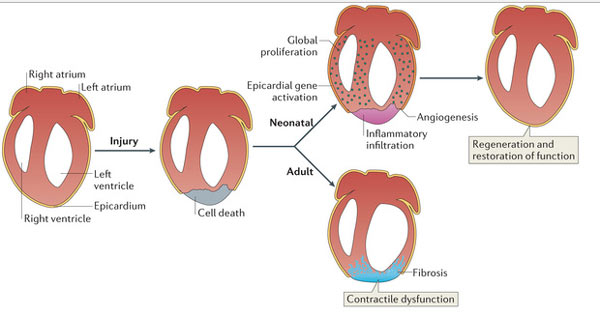

ইঁদুরের হার্টের কোষ, কলার রিজেনারেশনের ধাপগুলি

ইঁদুরের হার্টের কোষ, কলার রিজেনারেশনের ধাপগুলি

রিজেনারেশনের ধাপ (জেব্রাফিশ, ইঁদুর, মানুষ)